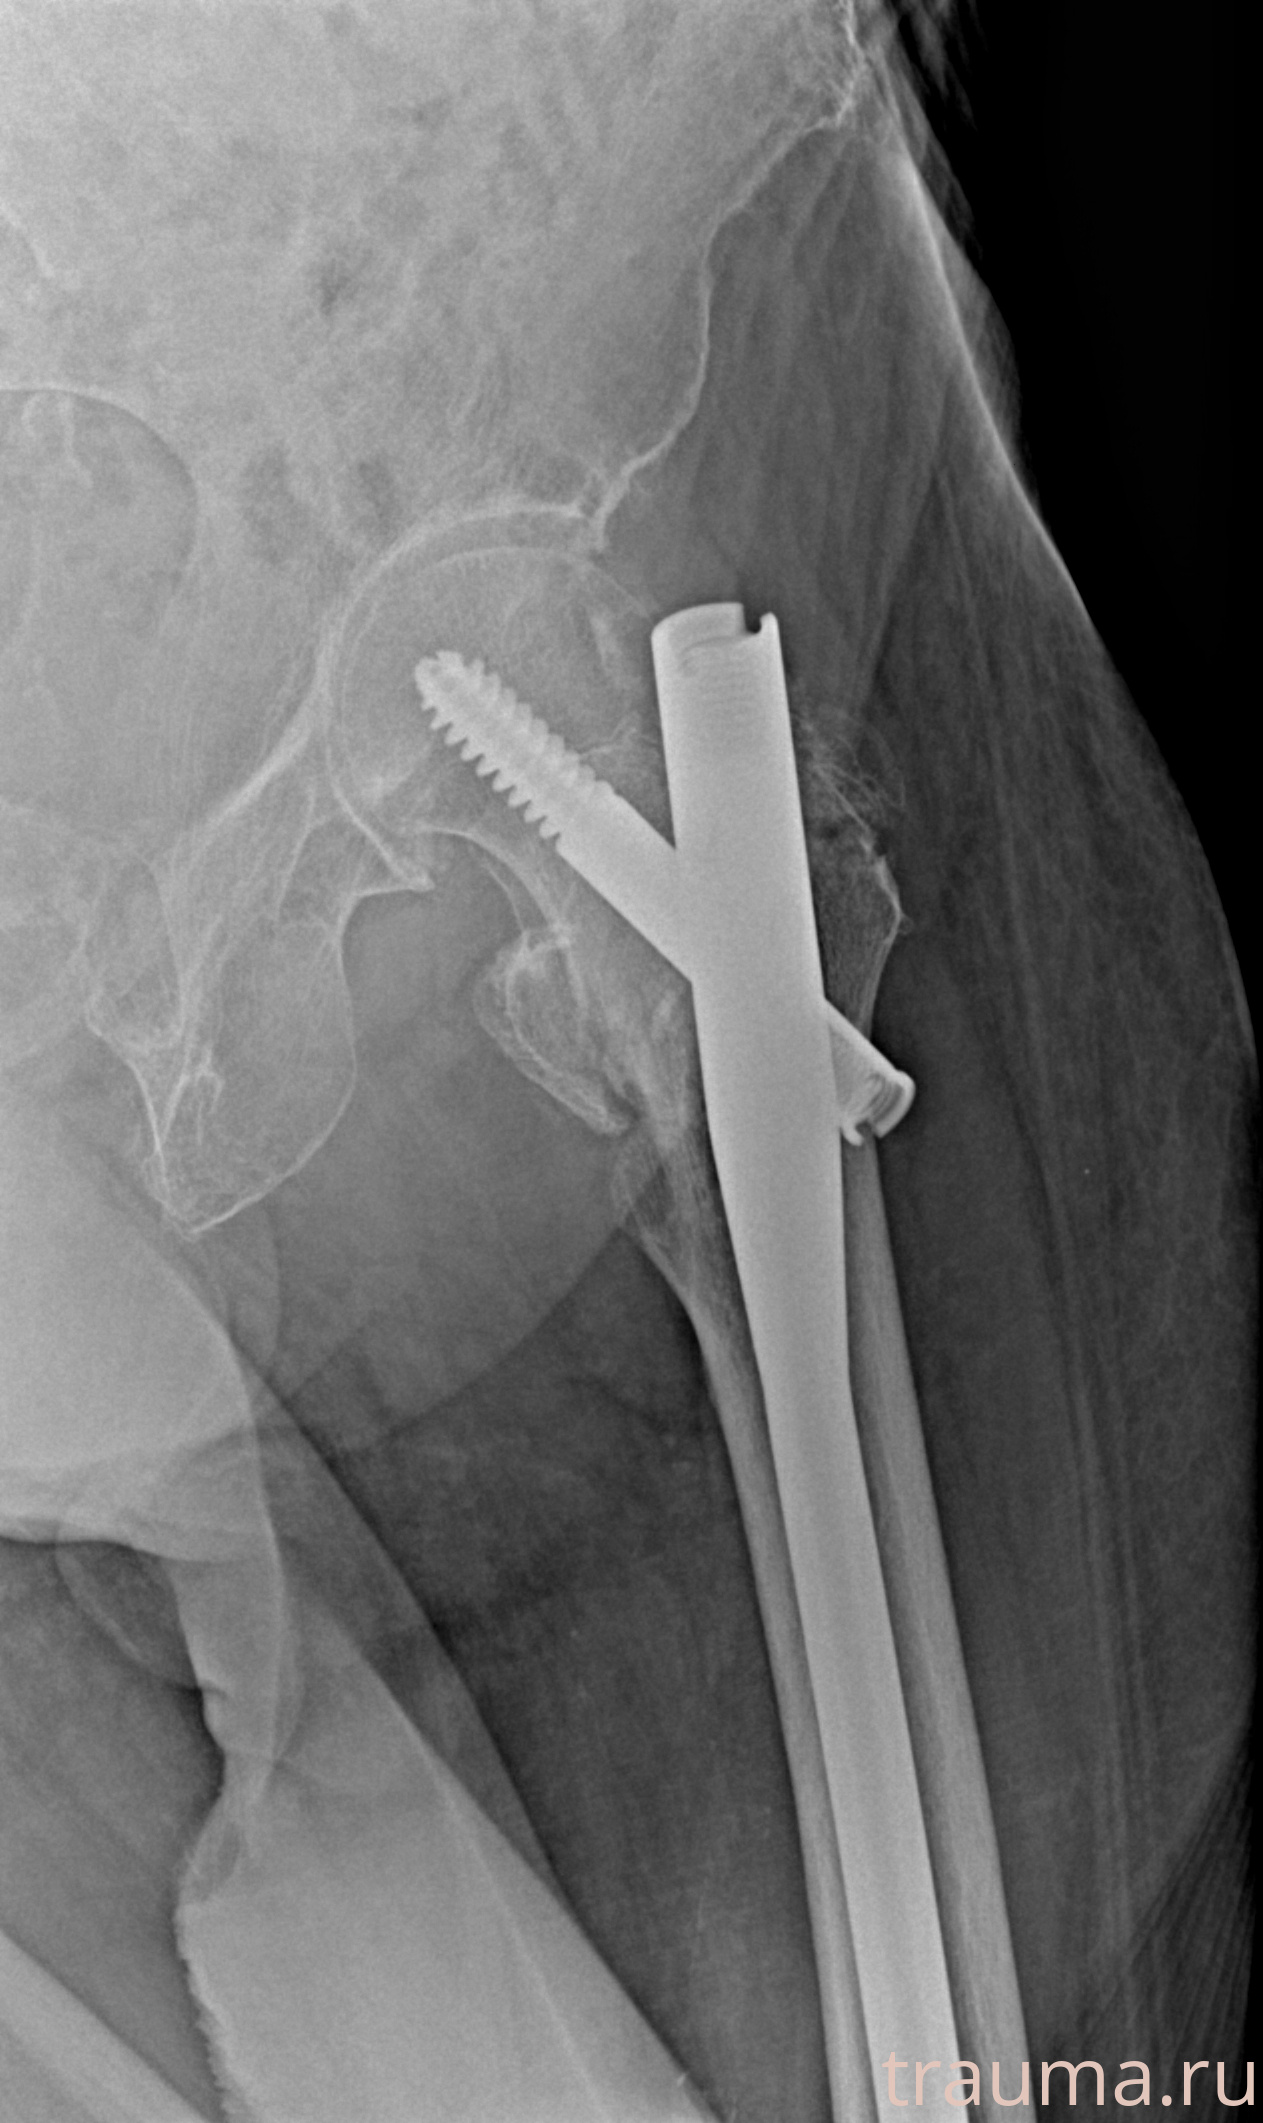

Рентгенограммы

Рентген на дому: по вашему адресу приезжает врач-рентгенолог, травматолог-ортопед с мобильным рентгеновским аппаратом, проводит диагностику травмы или заболевания, делает необходимые рентгенограммы, дает рекомендации по дальнейшему лечению. Получить качественные снимки в домашних условиях возможно благодаря уникальной методике, разработанной МосРентген Центром для института  Склифосовского